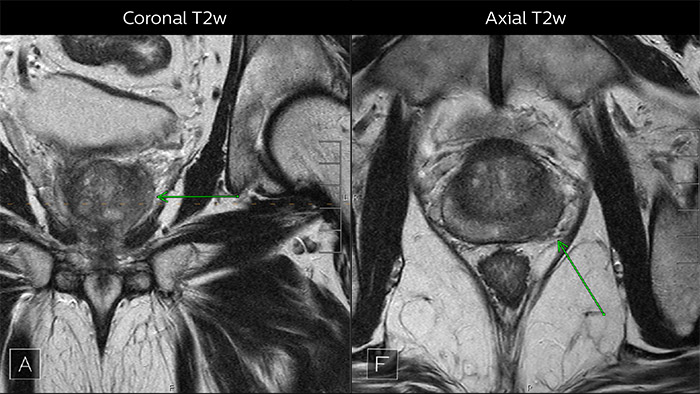

Для диагностики поражений в периферической области предстательной железы особенно эффективны диффузионно-взвешенная визуализация (DWI) и карта ADC. В данном случае DWI показала очень яркий сигнал, что указывает на ограничение диффузии. Дугообразная область со значительным выпадением сигнала (стрелка) на карте ADC обозначает высокую вероятность наличия опухоли. На T2-взвешенном изображении в аксиальной проекции контур капсулы немного неровный (стрелка), что мы интерпретируем как разрушение капсулы, и я обычно выполняю измерение: данное поражение вызвало разрушение капсулы более чем на 1,5 см. Я не вижу признаков лимфаденопатии, но причисляю это поражение к категории PI-RADS 5. На нижних изображениях (Динамической МРТ с контрастным усилением) видна картина, характерная для гиперваскулярной опухоли, что подтверждает точность диагностики.